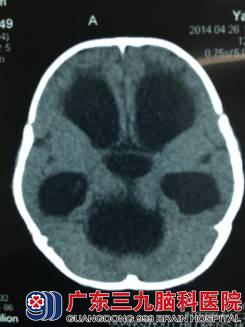

患儿洋洋(化名),女, 8个月时仍不能抬头、翻身等,到外当地医院检查头部CT,显示:小脑上池蛛网膜囊肿合并脑积水,医生为其行脑室腹腔引流术,术后1个月复查头部CT显示脑室缩小,但原蛛网膜囊肿仍继续增大,压迫了脑干。

头部CT可见脑室扩张明显,分流管位于脑室内,蛛网膜囊肿增大,压迫脑组织。